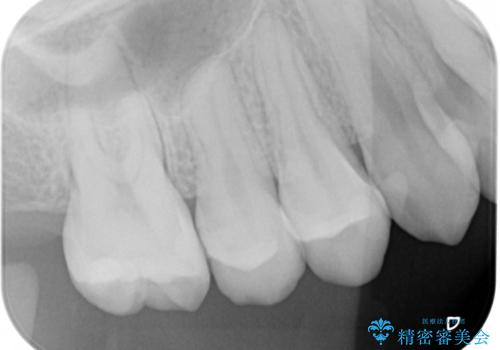

変色した詰め物の再治療 セラミックインレー

- 以前保険で治療した詰め物の変色を治したいとの主訴でご来院されました。

審美性と耐久性に優れたセラミックインレーで治療しました。

歯の一部が虫歯になってしまった場合の治療法のひとつにインレーがあります。

虫歯になってしまった部分を含めて詰め物用に形を削り整え、型取りをし、出来上がってきた技工物をセメントで接着します。